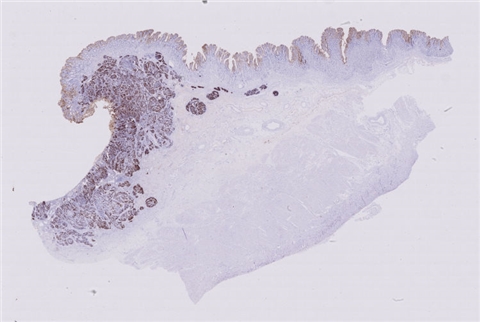

案例9 (6975)

性别:       年龄:41

患者详情: 患者于半年前无明显诱因出现大便带血,为暗红色血便,未见粘液脓血便,反复发作,无腹痛腹胀,伴大便次数增多,并大便不成形,逐渐变细,初未引起重视,亦未行相应治疗,后症状逐渐加重。为进一步诊治,2020年3月入住我院。 直肠指诊:括约肌紧张度:正常,狭窄:无,触痛:无,距离肛门口大约4cm可及一环直肠一周肿块,质硬,移动度差,无压痛,指尖稍可通过肿块,指套染血:有。 电子肠镜示:距肛门4cm直肠处可见一巨大新生物,中间凹陷,底覆污秽苔,环2/3腔生长,钳取6块送病理,余 结肠各段粘膜光整,血管纹理清晰,未见明显的溃疡、息肉。 活检病理示:恶性肿瘤。后行腹腔镜直肠癌根治术。

大体所见: 1、直肠癌肿物:已切开肠管一段,长10cm,一侧切缘周长4cm,另一侧切缘已缝合,长3cm,紧邻缝合切缘见一溃疡型肿物,大小4.5*4*3cm,肿物切面灰白灰黄色、质硬,与周围组织分界欠清,侵及全层。

2、上切缘:灰褐色黏膜组织一块,大小1*1*0.4cm。

3、下切缘:灰褐色黏膜组织一块,大小1.2*1*0.4cm。

免疫组化: 2002032-004#:CgA(弱+)、syn(+)、CD56(+)、 2002032-002#:CK(+)、TTF-1(+)、CD34 +、SMA(-)

医院: 赣南医学院第一附属医院